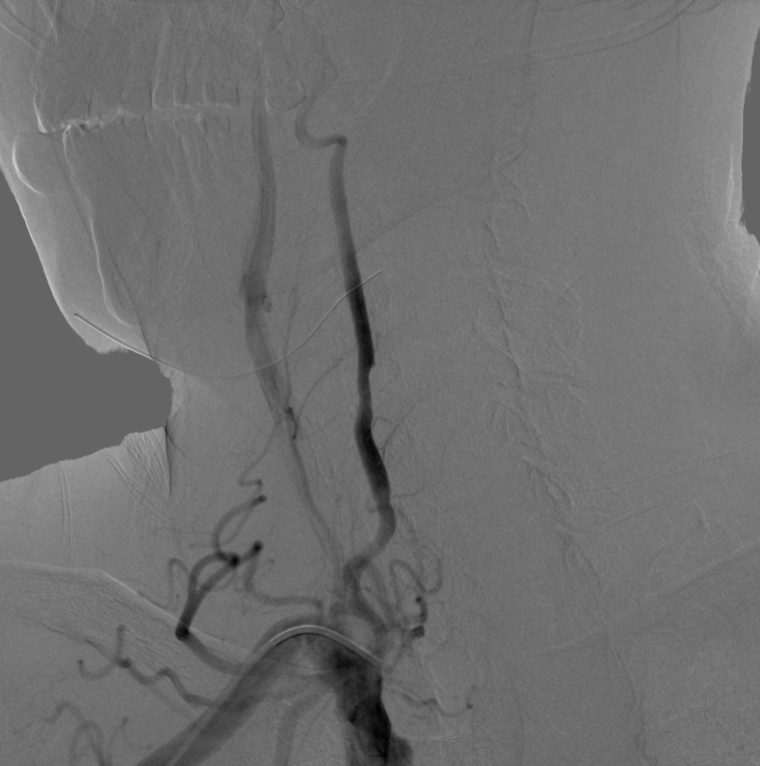

术后造影:

左侧颈内动脉C1段残余狭窄约10%,远端血管显影良好,前向血流mTICI 3级,未见远端血管栓塞及造影剂外渗。